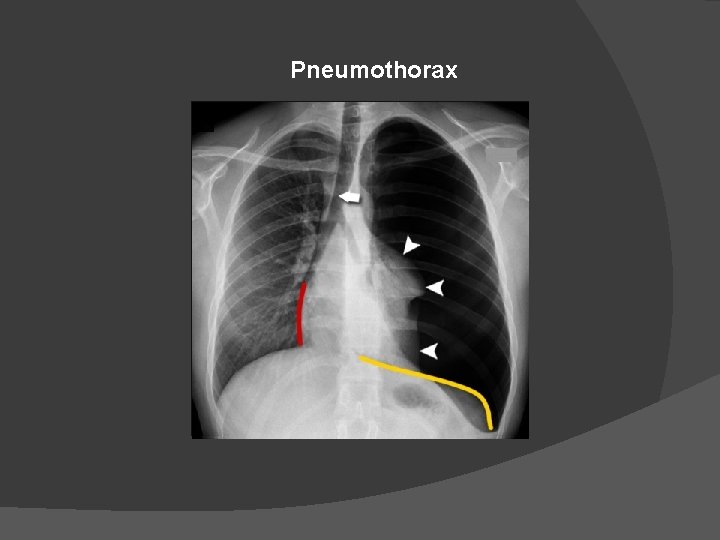

Pneumothorax